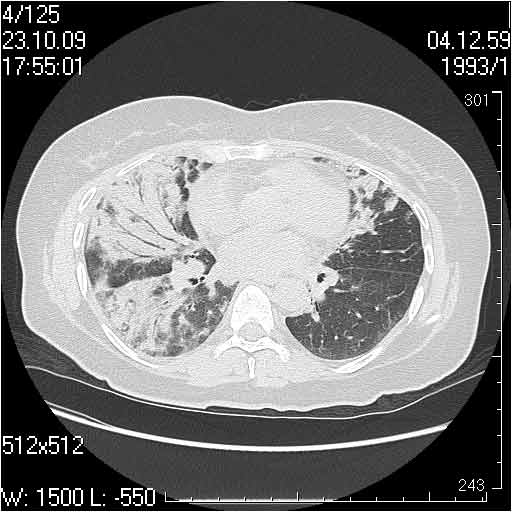

Случай №1

Женщина 50 лет.

Случай 1: изменения характерны для интерстициальной пневмонии (IIP/UIP idiopathic interstitial pneumonia/usual interstitial pneumonia); говорить о конкретной форме без открытой биопсии затруднительно.